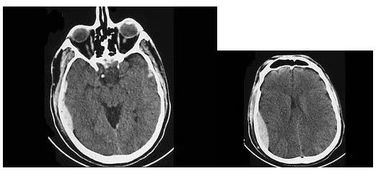

1. 更高的图像分辨率:CT可以提供横断面图像,图像分辨率高,可以清晰地显示组织结构和器官的细节,有助于更准确地诊断疾病。

CT扫描通过精确的X射线束对人体进行扫描,能够获得高清晰度、高分辨率的图像。这些图像可以清晰地显示人体内部的器官和组织结构,对于诊断疾病具有重要意义。与X光相比,CT图像的分辨率更高,能够更准确地识别病变。

CT扫描适用于各种疾病的诊断,如神经系统、心血管系统、呼吸系统、消化系统、泌尿系统等。在X光检查中,由于图像质量有限,一些疾病的诊断可能存在困难。而CT扫描可以提供更全面、准确的诊断信息。